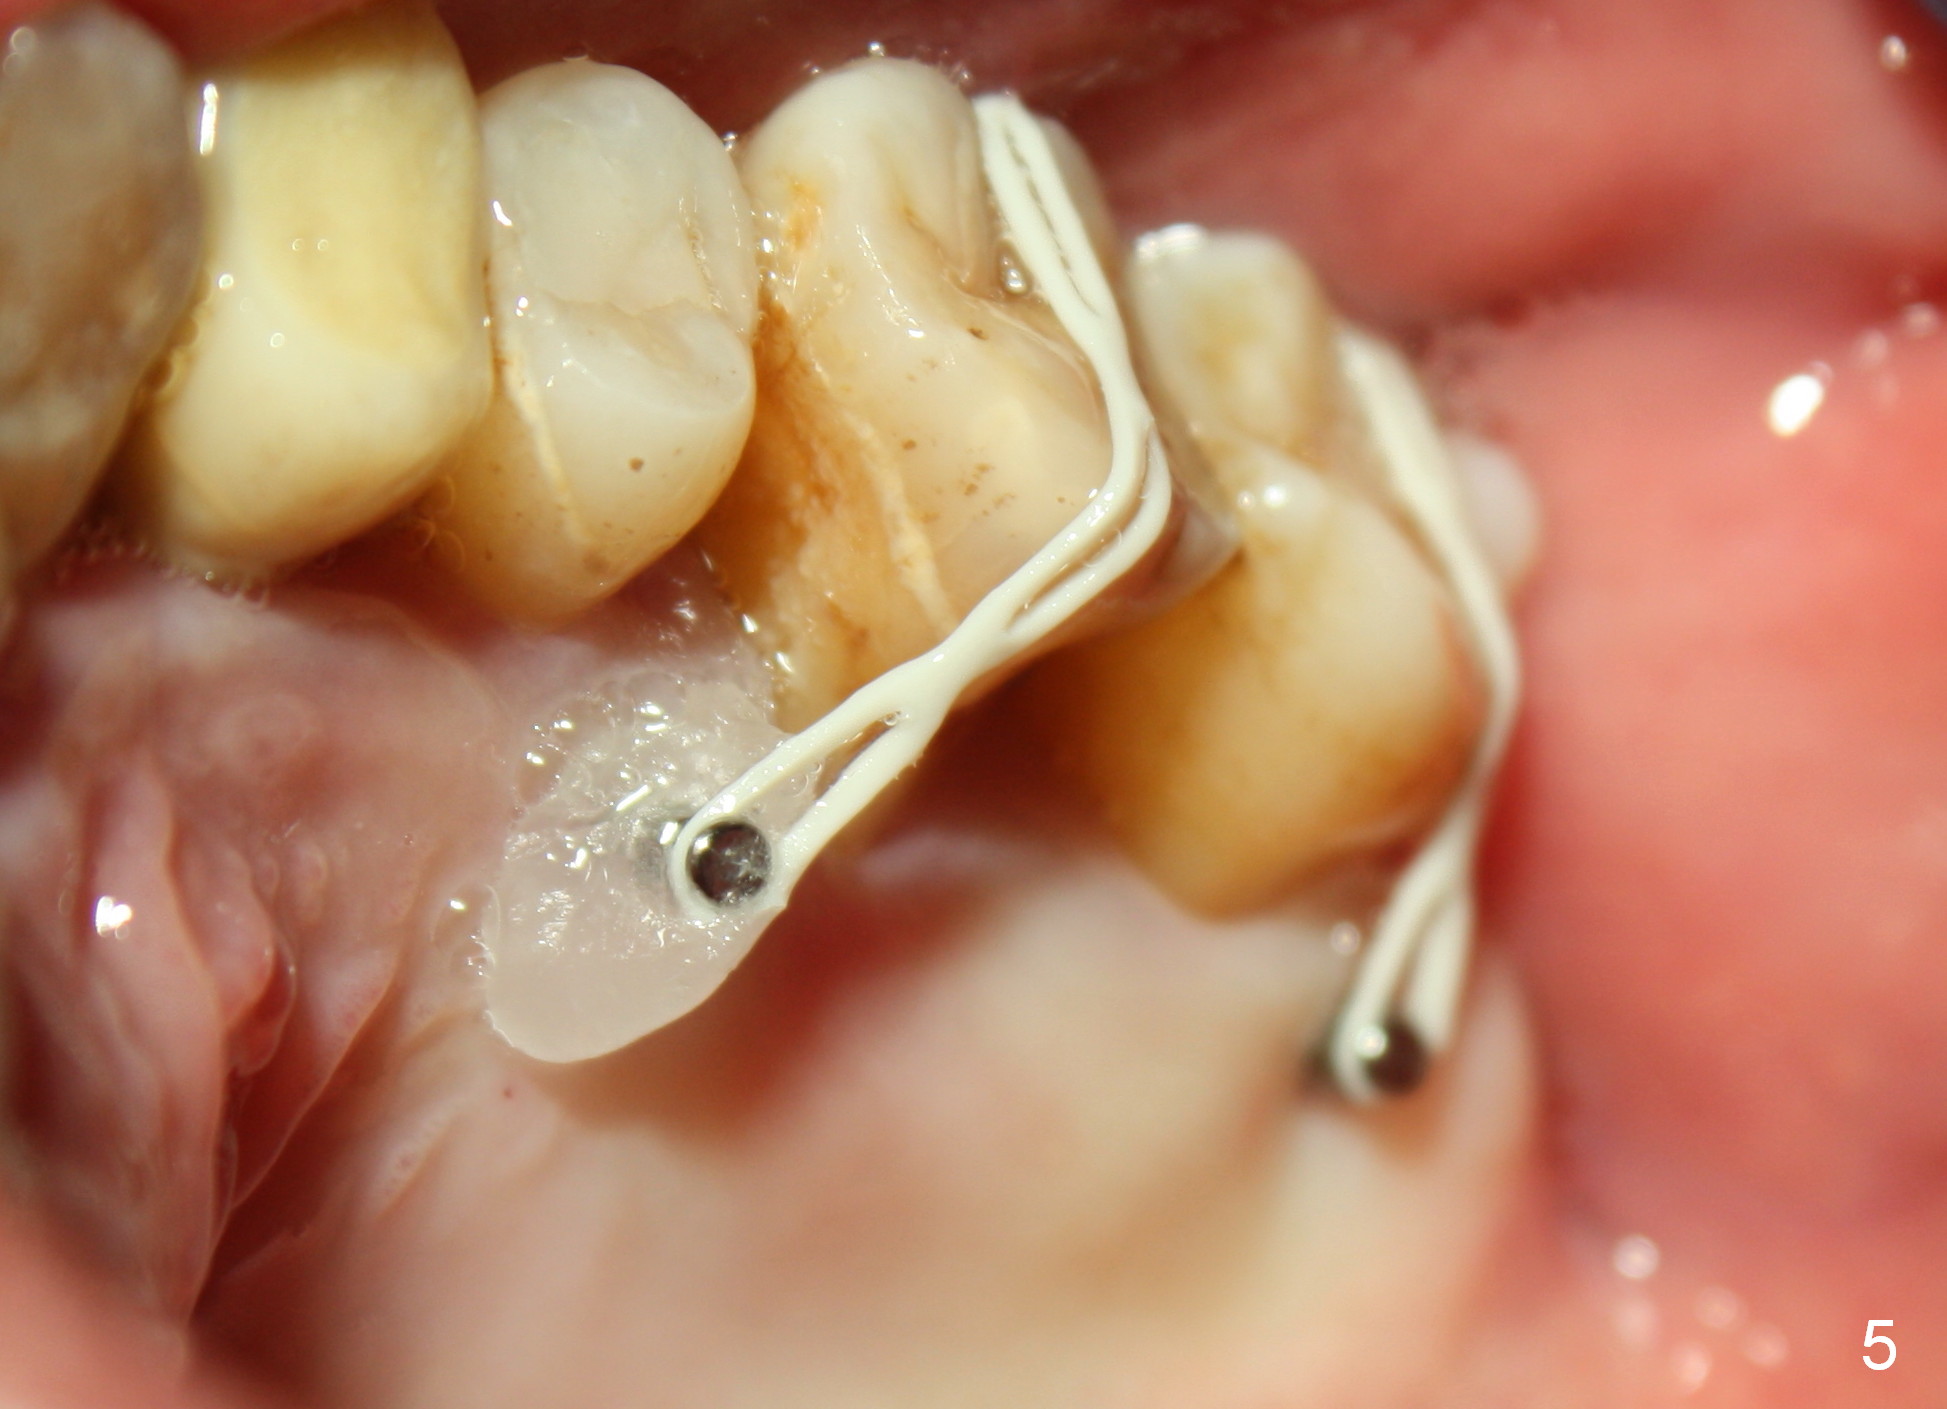

A 41-year-old man has chronic periodontits with bruxism. The teeth #14 and 15 are supraerupted (Fig.1 arrows) with furcal lesion (Fig.2 (CT) *). These 2 molars have guarded to poor prognosis. Due to insurance benefit limitation, we plan to save them temporarily with periodontal surgery so that bone loss would not get worse when the teeth are being intruded. After opposing implant placement (Fig.3), flaps are raised to remove calculus and granulation tissue (Fig.4, no bone graft). Twenty days later, three mini-implants are placed (Fig.5,6). The implant distopalatal to #15 is loose nearly 2 months postop (Fig.7 *) and retightened. The following month the same implant is placed higher for stability (Fig.8). The Intrusion takes <5.5 months (Fig.9,10).